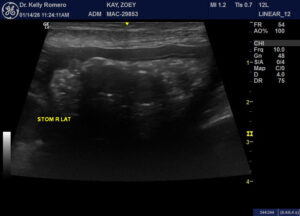

9 year old FS Shepherd cross losing weight, intermittent vomiting, diarrhea that has been worsening now with blood. Do you think these structures in the stomach lumen could be polyps? So far, planning to recommend endoscopy.

Looks like a rubber ball to me but ensure no pill pockets given as they look like this too. If its persistent at npo in followup scan i would cut or scope

Thank you, Eric. It didn’t seem to move in different positions, but the dog is not fully fasted and maybe it is sticking to the wall. Any concerns about the homogenous structure in the body lumen?